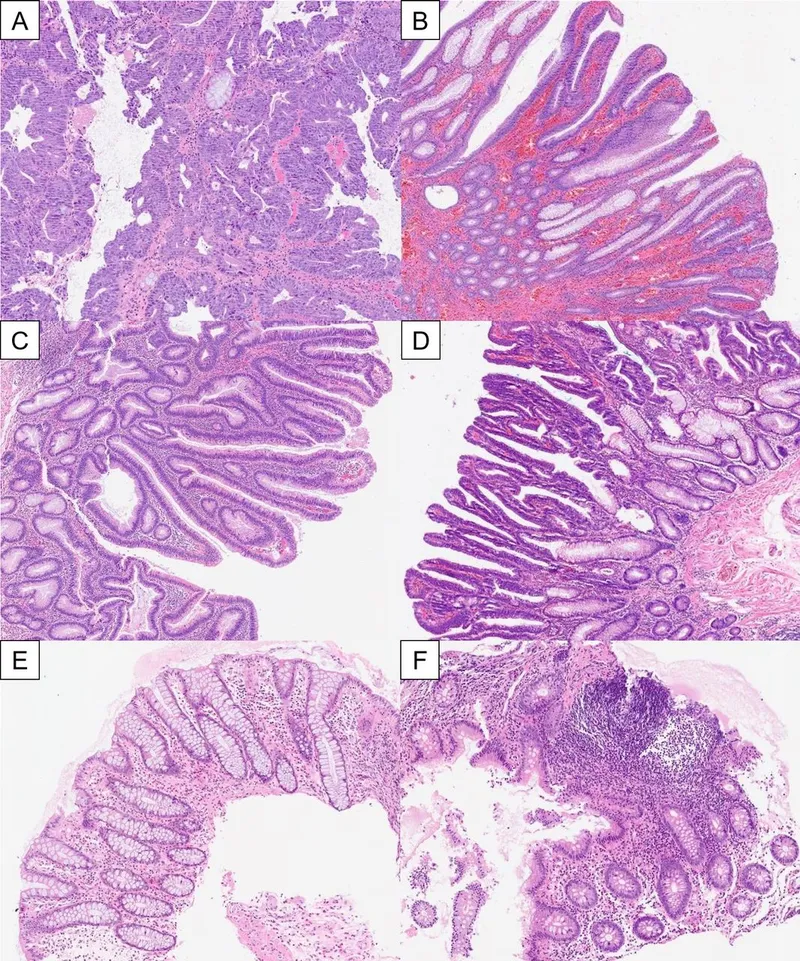

- Histologic Types:

- Tubular: Most common (~75%); pedunculated, smaller, lower cancer risk.

- Villous: Sessile, larger, high malignant potential. 📌 Villous is villainous.

- Tubulovillous: Mixture of features.

- Malignant potential correlates with ↑ size (>2 cm), ↑ villous histology, and high-grade dysplasia.